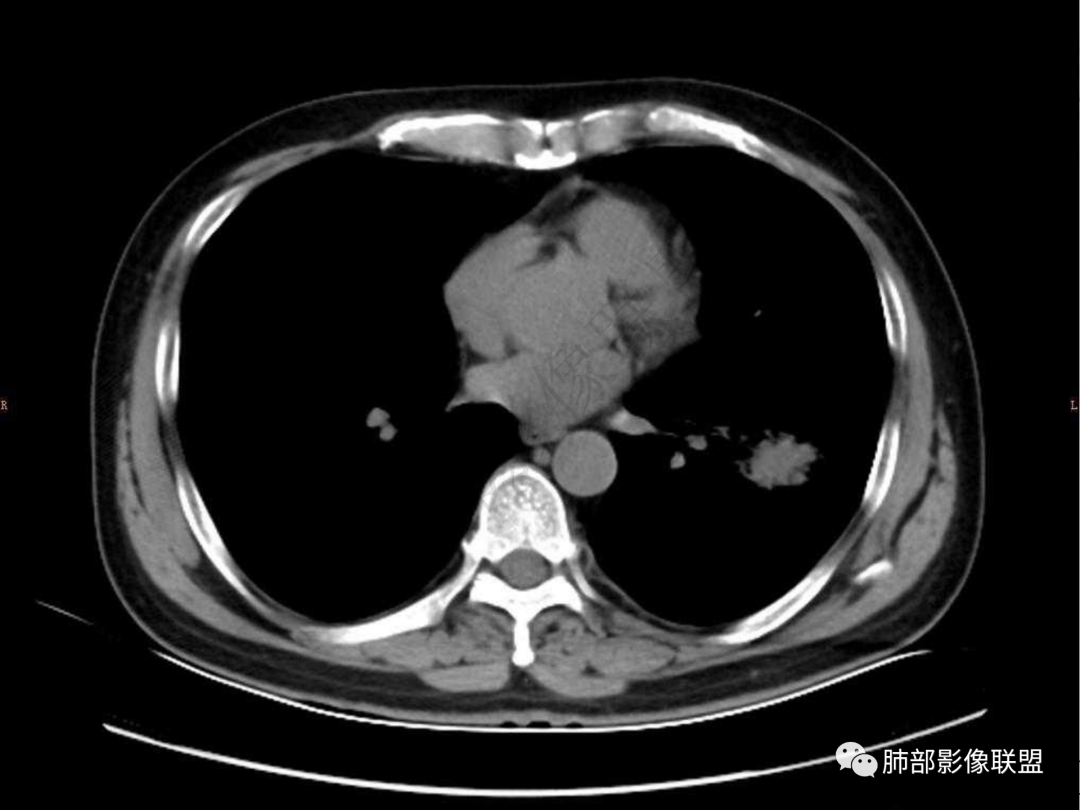

2.左肺下叶团片影,跨背段及内前基底段,实性部分类椭圆形,密度不甚均匀,可见毛刺及棘状突起,未见典型分叶及胸膜凹陷。病灶上下缘可见相应肺段支气管旁进侧出,管壁轻度增厚,未见狭窄阻塞。

3.周边较大范围磨玻璃影,边界相当模糊,小叶增厚明显。注意叶裂另一侧、左肺舌段亦可见磨玻璃影及增厚的小叶间隔。未见明确卫星病灶。

4.实性部分不均匀环形强化并显示一小范围低密度坏死区或空洞。较之肺窗,整体纵隔窗范围较小,提示病灶并不十分密实。抑或为不同时段图像。

5.双肺门及纵隔未见增大淋巴结。未见胸腔积液。